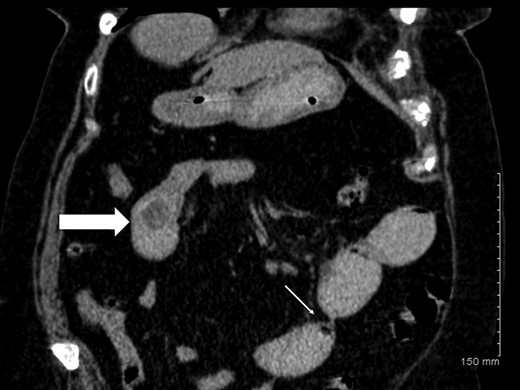

A plain abdominal radiograph was also unrevealing. She proceeded to have computerized tomography (CT) scan of her abdomen and pelvis, which showed dilated small bowel loops consistent with small bowel obstruction. There were two filling defects noted, one in her proximal ileum suspicious for a non-calcified gallstone and the second distally in her terminal ileum (Figs 1 and 2). Appearances were suggestive of gallstone ileus. She was adequately resuscitated and underwent a laparotomy. The small bowel was narrowed in two segments: proximally secondary to an impacted gallstone and an area of stricturing noted distally. Both segments were resected with end-to-end anastomosis performed in a two-layer standard hand-sewn fashion. The clinical impression was one of dual pathology including Crohn's disease and gallstone ileus. She did not undergo a cholecystectomy or repair of her cholecystoduodenal fistula. She made an uneventful post-operative recovery and was discharged home well on Day 7.

Coronal CT image demonstrating gallstone ileus (block arrow) and stricture in distal ileum (thin arrow).